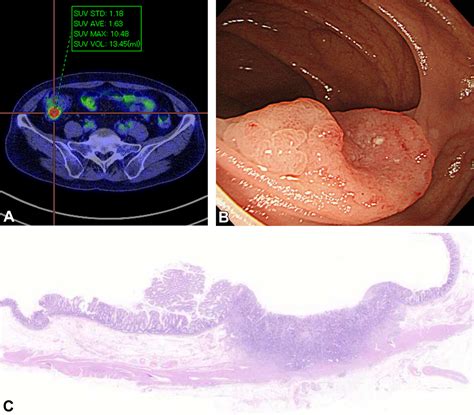

To understand a Sessile Serrated Adenoma, it helps to break down the medical terminology. "Sessile" indicates that the growth is flat or broad-based, rather than having a stalk like a mushroom. "Serrated" refers to the saw-toothed appearance of the cells when viewed under a microscope. Finally, an "adenoma" is a type of tumor, though in the context of colon polyps, it refers to a non-cancerous growth that, if left alone, may undergo genetic changes leading to malignancy.

The primary goal of colorectal cancer screening is to find and remove polyps before they have the chance to transform into cancer. Because Sessile Serrated Adenomas are notoriously difficult to see, high-quality colonoscopy—performed by an experienced gastroenterologist—is vital. They often appear pale, are covered by a layer of mucus, or have a subtle change in the texture of the colon lining, which can make them camouflage against the surrounding healthy tissue.

The diagnosis is made definitively during a colonoscopy. If your doctor spots a lesion, they will perform a polypectomy (the removal of the polyp) using specialized instruments passed through the colonoscope. The removed tissue is then sent to a pathology lab where a pathologist examines the cells under a microscope to confirm the diagnosis and ensure the margins are clear.